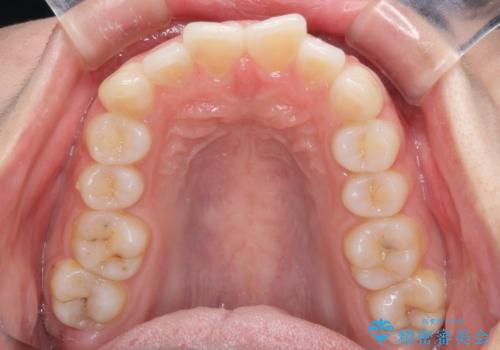

- 前歯のデコボコを気にして来院された患者様です。

当初は口元の突出感はあまり気にされていない様子だったので、インビザラインによる非抜歯矯正をお勧めしたが、ふっくらとした口元を改善したいとのことで、積極的に口元の突出感を改善することとしました。

上下左右第一小臼歯4本の抜歯を行い、ワイヤー装置による矯正治療を行うこととしました。